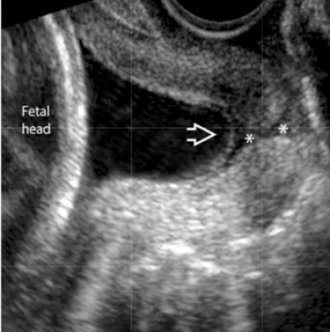

SONO: cervical cerclage

post-cerclage procedure; imaged transvaginally

cerclage stitches are echogenic with posterior shadowing

serial scans may be done to ensure cerclage remains secure and cervix is closed

what are the arrows pointing to?

cervical cerclage stitches